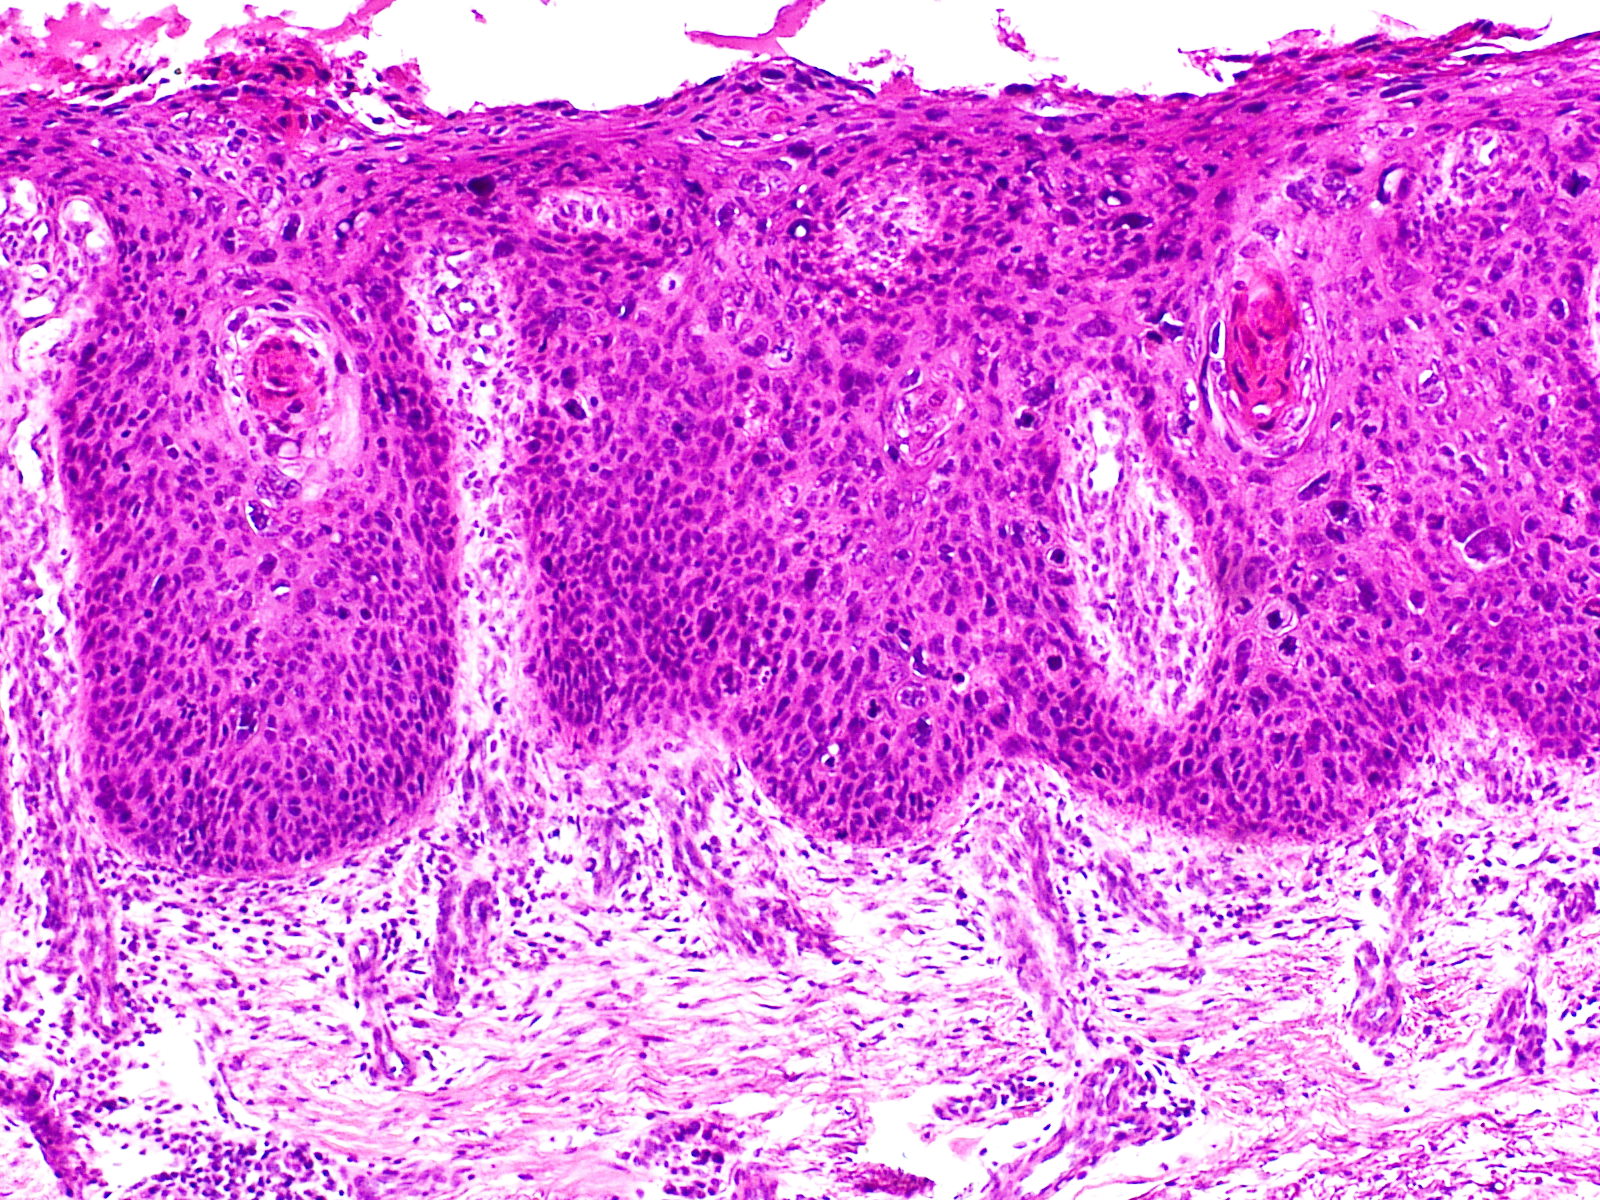

Histologie:M. Bowen

is een intra-epidermaal spinocellulair carcinoom, een 'carcinoma in situ'. In

het sterk acanthotische epitheel ziet men onder een deels hyperkeratotische

deels parakeratotische hoornlaag, hoe wanordelijk de cellen zijn gerangschikt;

er zijn vele kern- en celatypien, irregulaire kernvormen, atypische celdelingen,

reuscellen, pycnotische kernen en individueel verhoornde cellen met pycnotische

kernen (dyskeratose); ook hoornparels komen voor. Het stratum basale is intact

en er is geen infiltratieve groei. Treedt metastasering op dan zijn de basale

laag en de basale membraan wel doorgroeid door de anaplastische cellen en gedraagt

de tumor zich als een spinocellulair carcinoom. Deze doorgroei kan soms pas

na jaren optreden, maar bij m. Queyrat ziet men dit doorgaans veel sneller gebeuren.

In de cutis bestaat een banaal lymfocytair ontstekingsinfiltraat, soms gemengd

met plasmacellen.